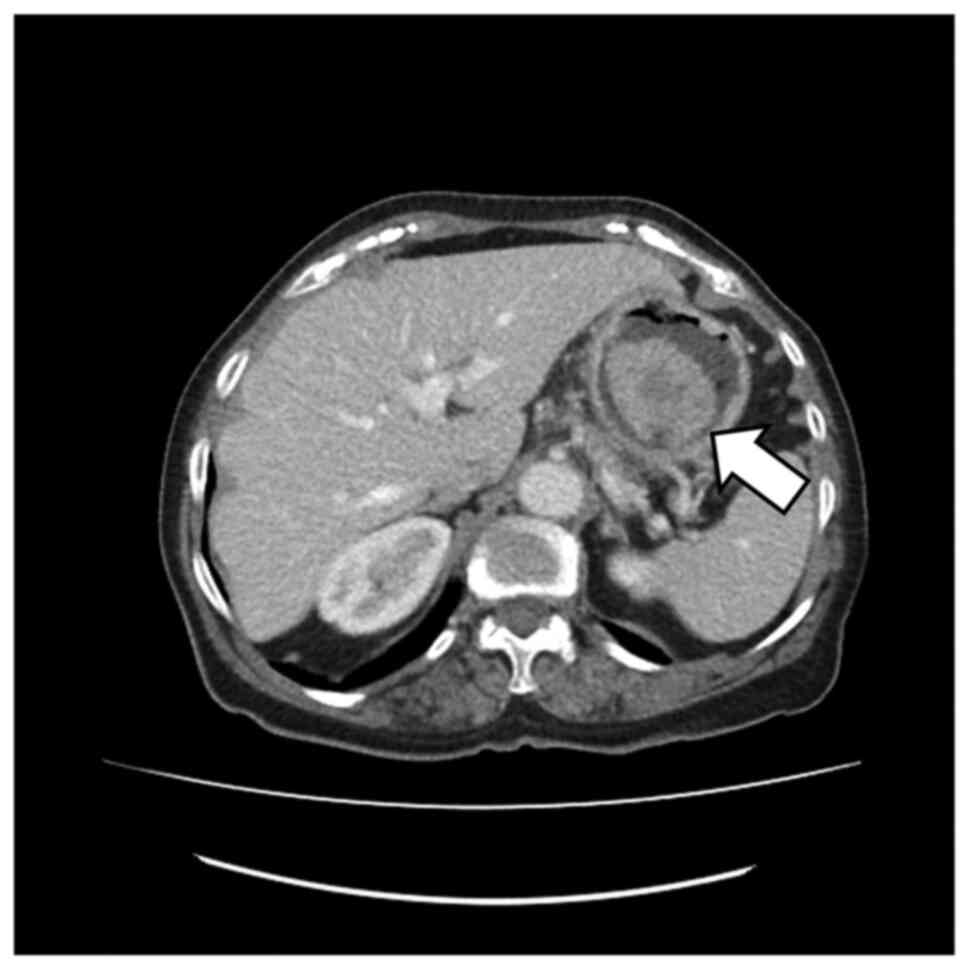

An unusual non‑metastatic, mismatch repair‑deficient primary gastric squamous cell carcinoma presenting as a large, exophytic, bleeding tumor: A case report

Primary gastric squamous cell carcinoma (GSCC) is an extremely rare malignancy with a poor prognosis. Despite the improved knowledge regarding its pathogenesis and biology, the treatment options remain limited. The present study reported on the unique case of a mismatch repair‑deficient (dMMR) primary GSCC in a 79‑year‑old woman reporting fatigue and symptoms of upper gastrointestinal tract bleeding. Physical examination revealed abdominal pain at palpation. Gastroscopy revealed a large, exophytic, bleeding tumor. Medical imaging confirmed a mushroom‑like polyp in the lumen of the stomach, with no signs of disease spread. Total gastrectomy and D2 lymphadenectomy were performed. Pathological examination of the post‑operational material confirmed a well‑differentiated SCC invading the mucosa, submucosa and muscle layer. There were no signs of dissemination observed in any of the 32 excised lymph nodes. Notably, according to the last follow‑up, the patient remains well, supporting the 5‑year GSCC survival rate statistics. To the best of our knowledge, this is the first such GSCC case reported in the Surgical Oncology Outpatient Clinic (Copernicus Memorial Hospital, Lodz, Poland) and these findings add to the limited data on GSCC. Although this is a very rare condition, it should always be considered during the process of diagnosis of gastric tumors.